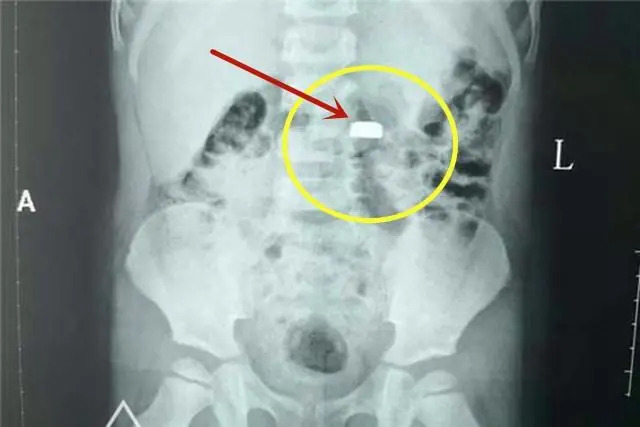

Viên pin cúc áo mà bé trai 3 tuổi của chị Linlin nuốt phải gây nguy hiểm dù tới bệnh viện ngay sau đó

Mắt đã ngấn lệ nhưng chị Linlin không tranh cãi với họ. Chị ôm con ra khỏi nhà, bắt taxi đến thẳng bệnh viện. Sau khi đứa bé được cấp cứu thành công, lấy được viên pin cúc áo ra ngoài, chị mới ngồi bệt xuống hành lang bệnh viện mà khóc nức nở. Một vị bác sĩ tới an ủi chị và nói: " Chị xử lý như vậy là rất nhanh trí, rất giỏi. Chị chính là người cứu được thực quản của cháu bé".

Quan trọng nhất, cần nhớ, dù dùng mật ong hay phương pháp sơ cứu nào cũng phải đưa trẻ đi cấp cứu càng sớm càng tốt ngay sau đó. Thông báo rõ hoặc mang theo loại pin trẻ nuốt phải. Bác sĩ sẽ sắp xếp chụp X-quang, CT và ưu tiên phương pháp nội soi để gắp pin ra sớm nhất có thể, ngăn chặn hóa chất rò rỉ phá hủy nội tạng.